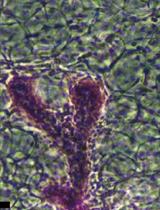

This protocol addresses a common challenge encountered when generating paraffin blocks from organoids cultured in BME. When fixation is performed directly on organoids embedded in BME, the matrix undergoes dehydration during processing, leading to collapse or distortion of the organoid structures (Figure 3). While densely packed cancer organoids, maintained primarily by strong cell–cell adhesion, often retain their morphology, cystic or balloon-like organoids—representing normal-like or loosely cohesive tumor phenotypes—are particularly vulnerable. For these morphologies, structural integrity relies heavily on BME support; thus, dehydration of the matrix frequently results in the collapse of the organoid architecture.

Figure 3. Limitations of the conventional formalin-fixed paraffin-embedded (FFPE) organoid preparation method. (A) Basement membrane extract (BME), indicated by black arrows, after the washing step. (B) BME collapse caused by dehydration following fixation. (C) Detached BME floating above the plate surface when fixation is followed by washing. (D) Complete loss of the 3D BME structure after washing. (E, F) Hematoxylin and eosin (H&E) staining of FFPE organoids prepared by the conventional method, showing loss of BME architecture and distortion of originally round, normal-like organoids that appear collapsed and misshapen. Stained slides were scanned using the Vectra PolarisTM Automated Quantitative Pathology Imaging System (Akoya Biosciences). The images were captured with the Phenochart software.